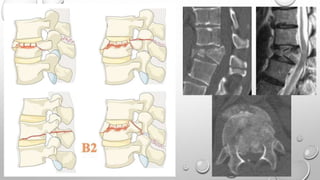

Tipo B

Describe falla del complejo ligamentario posterior

o el ligamento longitudinal anterior.

B1: Disrupción de la banda de tensión trans-osea

/ Fractura oportunista

B2: Disrupción de la banda de tensión posterior

B3: Hiperextensión